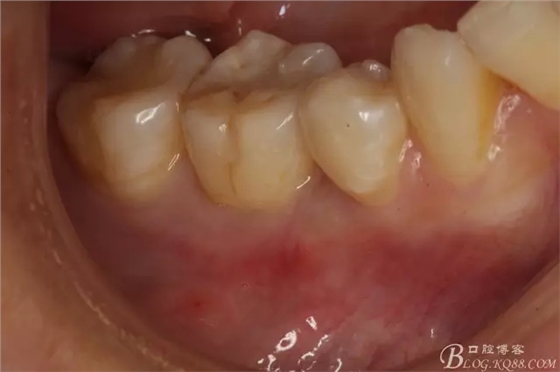

圖3.口內(nèi)頰側(cè)像,46、44鄰接正常,兩個牙頰側(cè)牙齦乳頭正常。45牙根完全埋伏于齦下。

圖4.舌側(cè)觀牙齦乳頭正常。